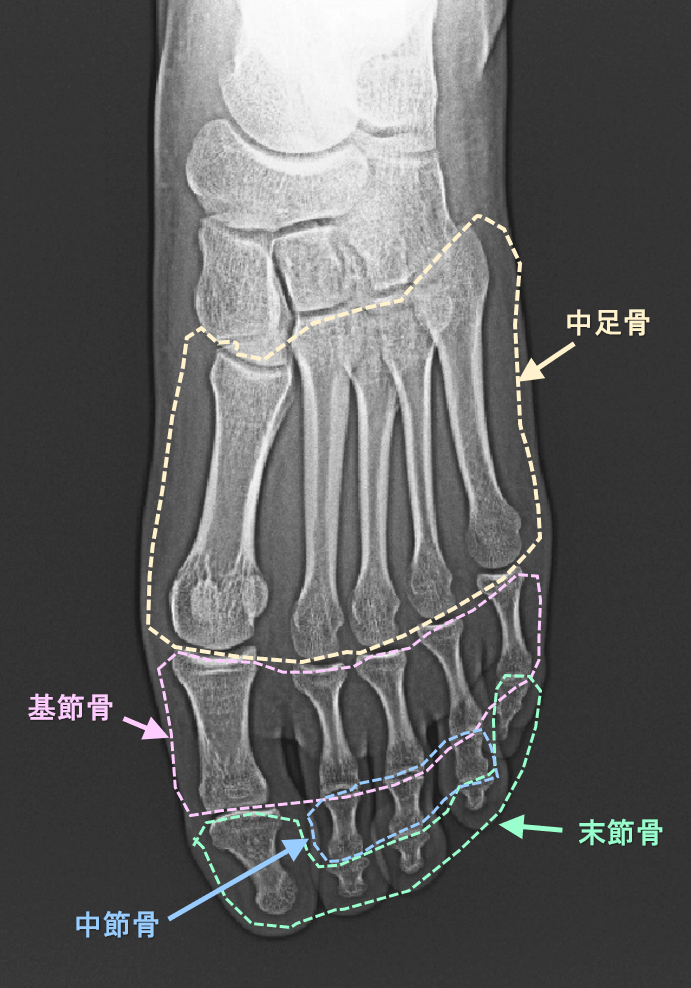

疲労骨折については、部位別の診療例の提示で“骨について”でも説明していますので、参照いただければ幸いです。まず、足部の骨の構造を提示しておきますが、中足骨という骨の列(親指から第1中足骨とし、第5中足骨まであります)の名称だけ覚えてください。

足指の骨の名称.png